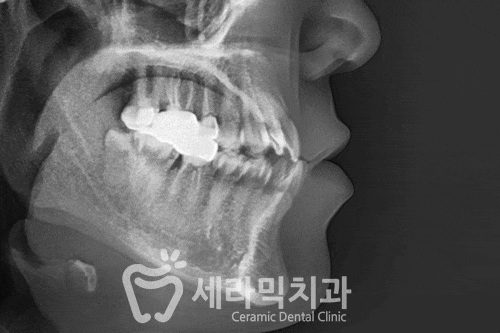

오늘 살펴볼 세라믹치과의 반대교합 치아교정전후 사례는

반대교합, 아래턱 돌출, 중심선 비대칭이 함께 나타난 경우입니다.

● 반대교합 치아교정전후 사례자 프로필

교정 시작 나이 : 25세

교정 시작 이유 : 반대교합

● 치료계획 상세

① 앞니 반대교합,

② 치아배열 좋지 않음, ③ 위 치열이 좁음,

④ 아래턱 돌출과 비대칭,

(예상 교정 기간 약 18개월)

● 치료 결과

(실제 교정 치료 기간 : 17개월)

반대교합과 불규칙한 치아배열이

고르고 건강하게 개선되었습니다.